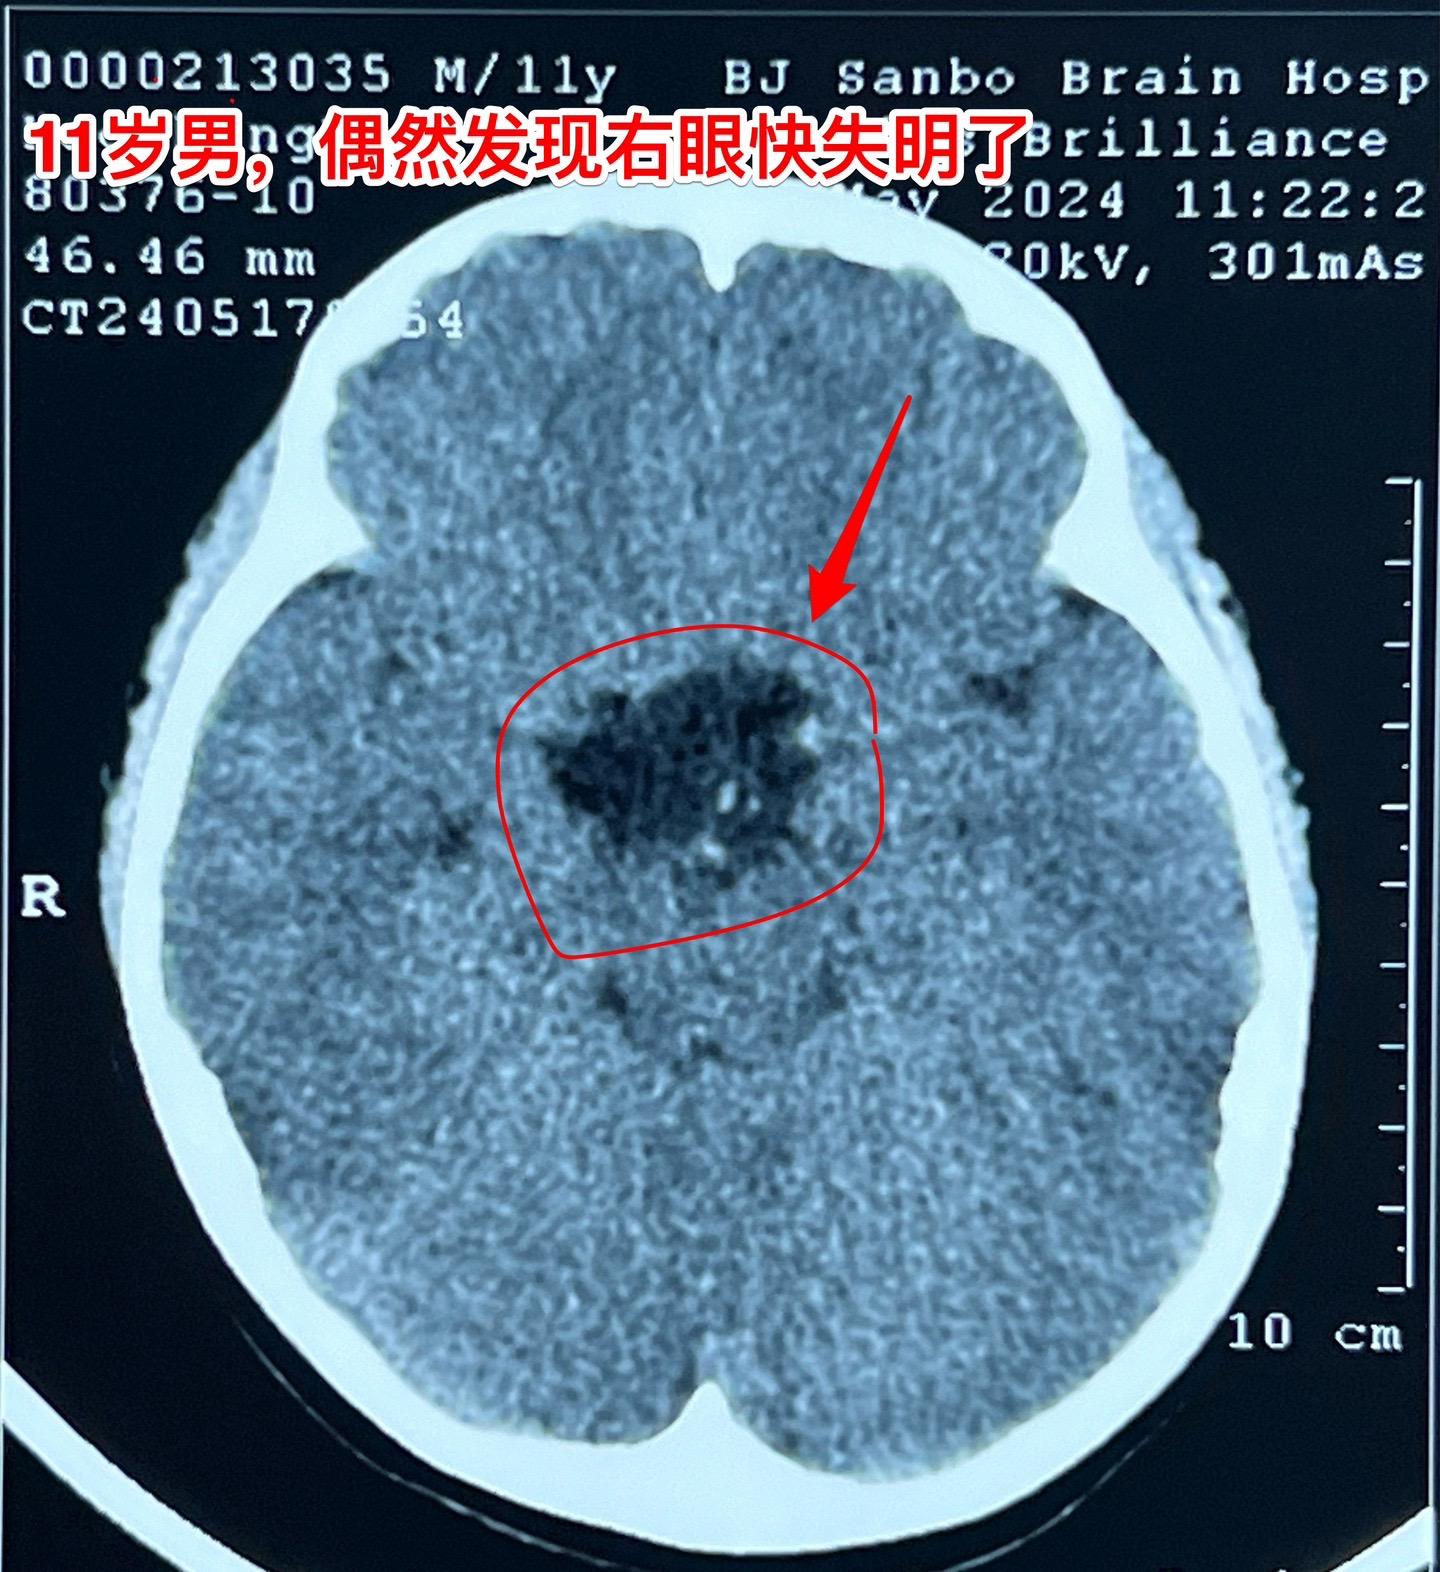

鞍区皮样囊肿比颅咽管瘤更罕见。11岁的湖北男孩子在学校体检查视力发现右眼几乎失明了,看不见东西,只有光感! 而他自己却不知道!平时也没有感到头痛,没有太多的不适。这个孩子是多粗心呀! 随后行脑部CT和磁共振检查发现鞍区 有个肿瘤,怀疑为颅咽管瘤。CT显示肿瘤没有钙化,这一点不符合颅咽管瘤。 5月31日作了开颅手术,将病灶完全切除。病灶的囊皮是灰色的,内部有油脂样的粘滞物,还含有毛发。所以术中诊断为皮样囊肿。这是近10年以来的第三例鞍区皮样囊肿手术。前两例